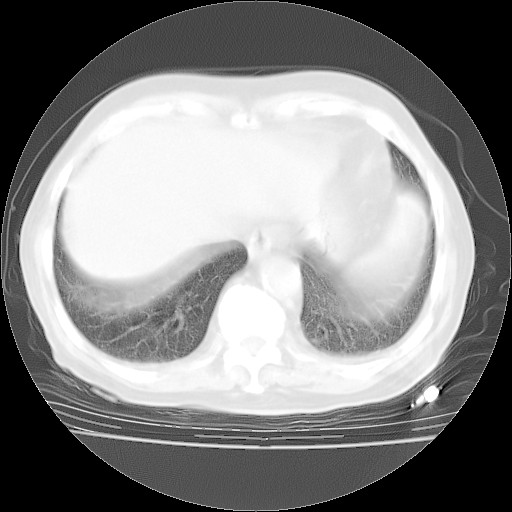

4月28日肺部CT——再次出现类似去年5月9日——透光度降低,“间质性”改变。

4月28日肺部CT——再次出现类似去年5月9日——磨玻璃样、间有“粟粒样”改变。

4月28日肺部CT